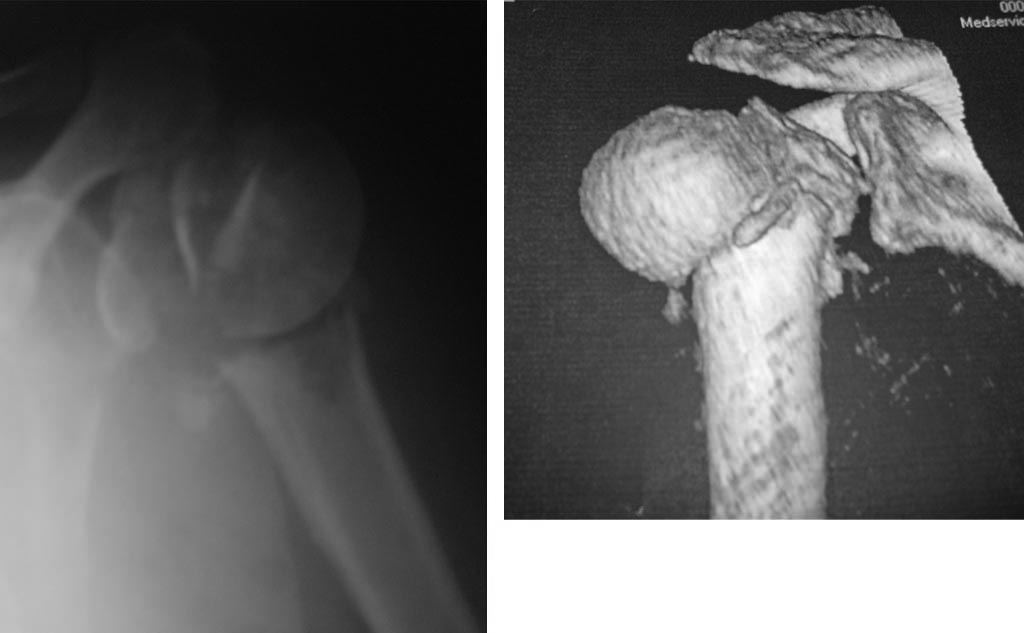

Да что Вы такое говорите, Юрий Алексеевич! Это самый что ни на есть махровый четырехфрагментный перелом, то есть анатомическая шейка плюс оба бугорка. Головка, можно считать, в вывихе, так что это ближе к 11-C3.2(2).

Анатолий Федорович, дорогой - чего там не видно на одном фасном снимкке, без КТ даже? Перелом по анатомической шейке виден? Бугорки отломленные видно? То, что суставная поверхность кнаружи-книзу смотрит, то есть вывихнута, видно?

Остеосинтез можно сделать хоть спицами, но надо в любом случае открываться, и не только вправить головку, но и фиксировать бугорки к плечу, то есть сухожилия прошить хорошо. В приложении картинки с аналогичным переломом.

согласен, перелом 4-х фрагментарный, при такой картинке, учитывая возраст, оптимальнее будет гемипротез.

Действительно данный перелом 4-х фрагментарный с вывихом головки плеча. При таком переломе,скорее всего,предпочтение надо отдать гемиартропластике.